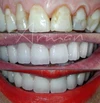

Zirkonyum uygulamalar

Porselen uygulamaları

Laminate veneer